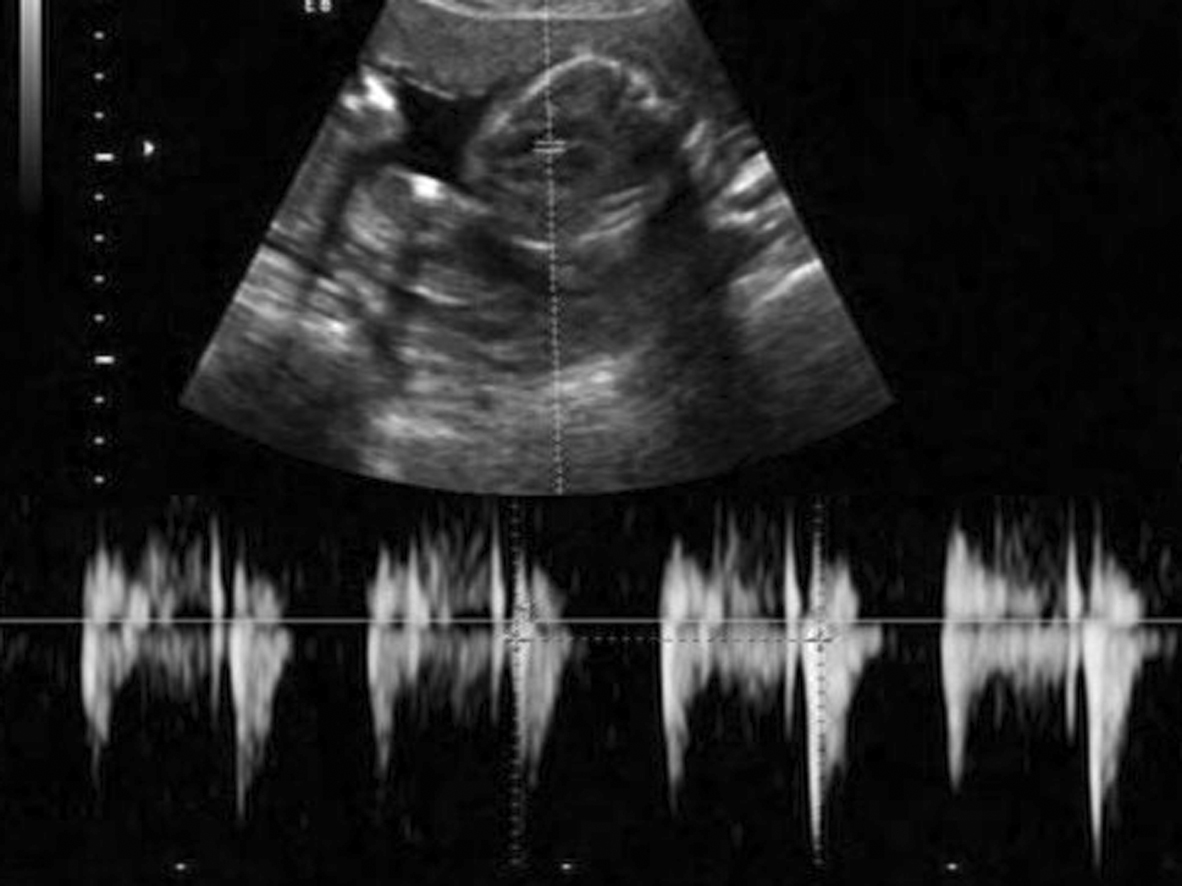

图2-A正常胎心显示规律的瓣膜活动曲线